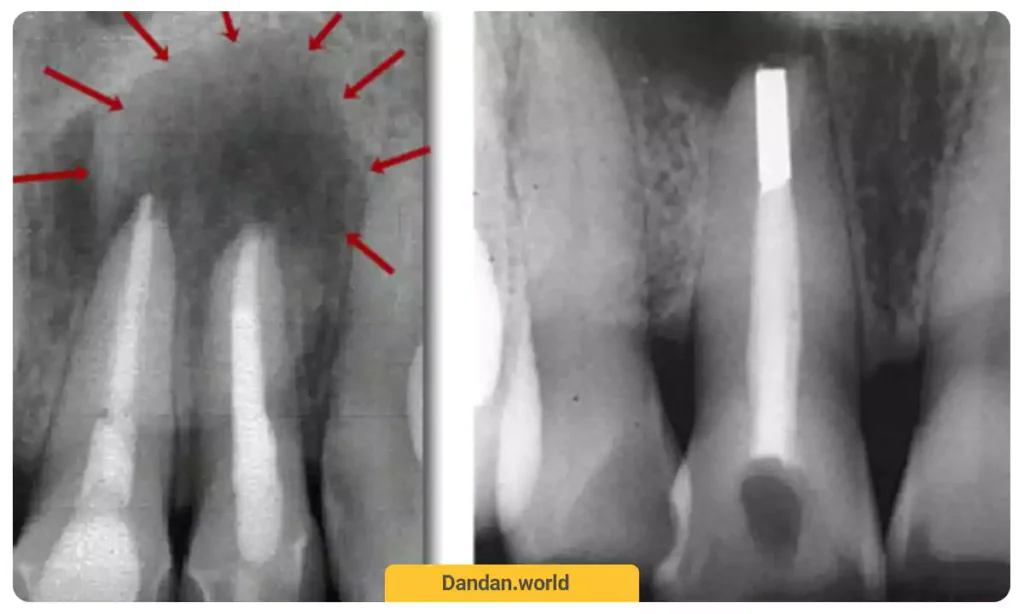

19. پست های دندانی (Posts in dentistry)

پست های دندانی در اصطلاحات دندانپزشکی دارای جایگاه ویژه ای می باشد. باید بدانید که پست های دندانی به 2 صورت پست ریختگی و پیش ساخته، طراحی و نصب می شوند. دندانپزشکان زمانی از پست های دندانی استفاده می کنند که تشخیص دهند دندان مرده است و دیگر دارای توانایی پشتیبانی کردن از باندینگ (روکش) یا بریج دندانی برخوردار نیست.

اگر دندانپزشک تشخیص دهد که دندان مرده است، هنگام پر کردن کانال های ریشه دندان از بین رفته، پست های دندانی را قرار می دهد تا ساختار دندانی قادر شود از باندینگ و بریج پشتیبانی کند. البته باید بدانید که در حال حاضر، پست های دندانی با جنس غیرفلزی بسیار مورد محبوب واقع شده اند.